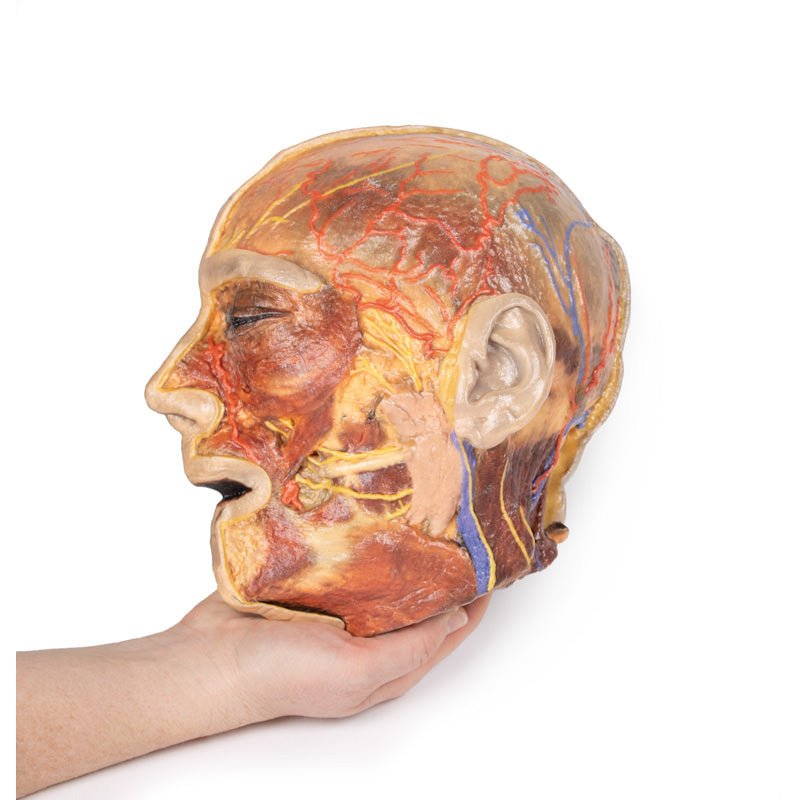

3D Printed Superficial Facial Nerves & Parotid Gland

This 3D model presents the superficial anatomy of the face and head, and compliments the superficial facial anatomy

of our HW 44 model with a more expanded dissection across the scalp and occipital regions.

The superficial

neurovascular and muscular structures in the face largely mirror the structures described in reference to our HW 44

specimen (see description), although the terminal branches of the facial nerve (CNVII) can be largely followed

across a longer course from the parotid gland and the platysma muscle has been retained superficial to the mandible

and extends towards the neck.

In contrast to the HW 44 specimen, this model has a more expansive superficial

dissection inferior to the external ear and across the posterior scalp and occipital region. This allows for an

expanded appreciation of the neurovascular distribution of the supraorbital and supratrochlear nerves and arties

with the superficial temporal artery. Inferior to the ear, the retromandibular vein has been exposed with the

ascending fibres of the great auricular nerve on its superficial surface (and further branches of this nerve on the

surface of the sternocleidomastoid muscle). At the posterior border of the sternocleidomastoid muscle the lesser

occipital nerve is just preserved, near the exiting and ascension of the occipital artery and vein near the

trapezius muscle towards the posterior scalp. Surrounding the external ear are fibres of the auricularis superior

and posterior muscles. Near the margin of the dissection window posteriorly the deep fibres of the occiptalis muscle

can be seen integrated into the epicranius (occipitofrontalis) muscle.